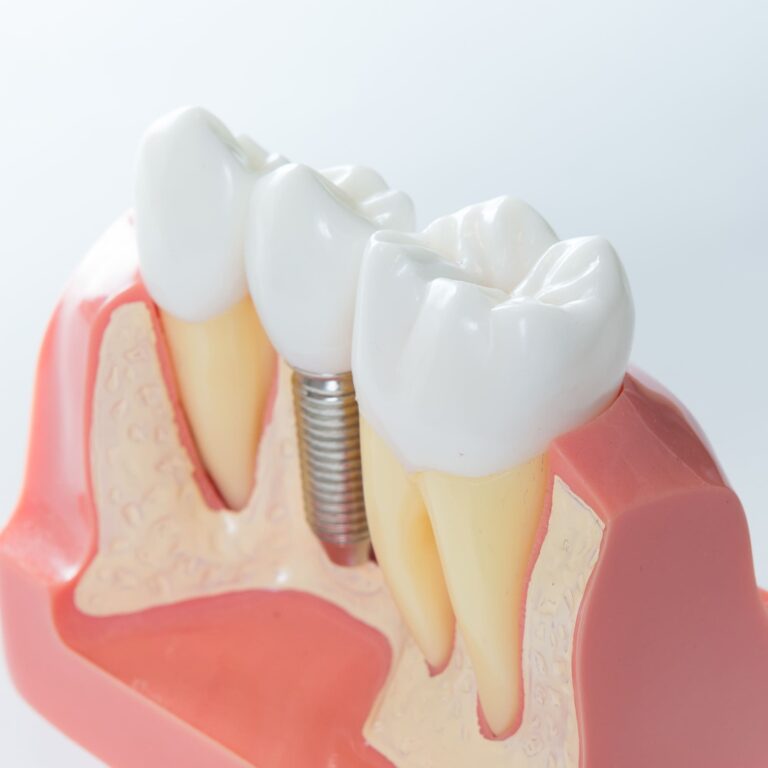

La gengivite e la parodontite sono malattie delle gengive e dei tessuti che circondano e supportano i denti e sono causate dai batteri contenuti nella placca e nel tartaro.